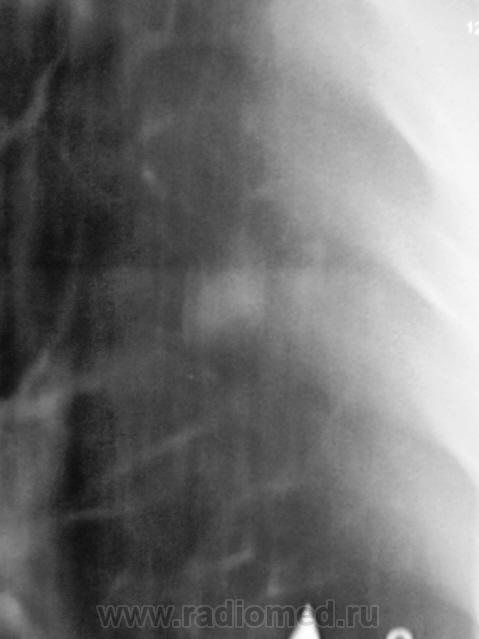

ТОМОГРАФИЯ.

Третий срез.